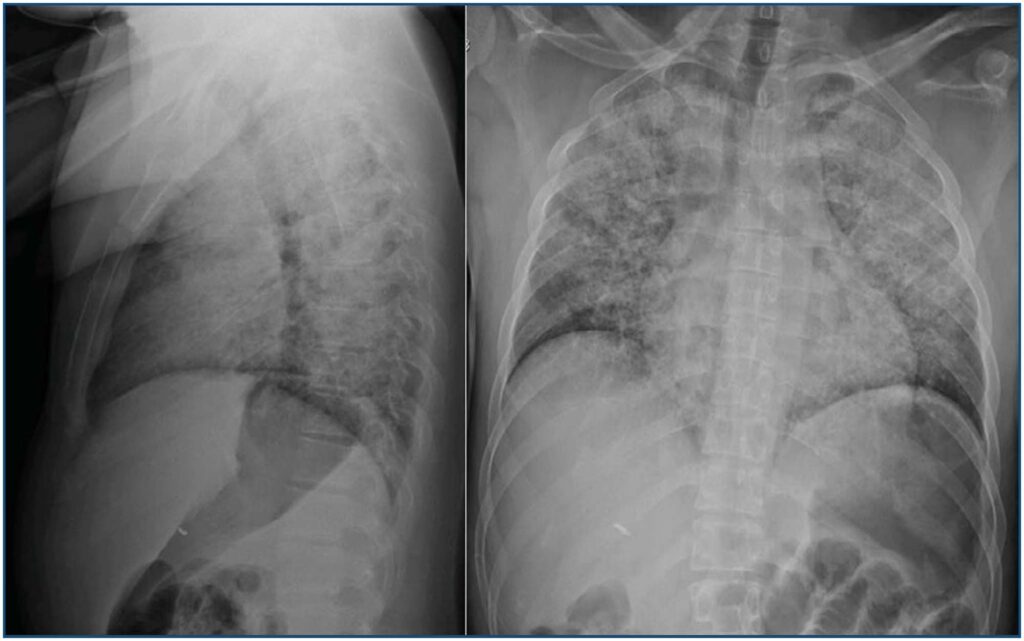

A doença falciforme é a hemoglobinopatia mais comum, e o período perioperatório pode apresentar exacerbação da doença. O objetivo deste relato foi descrever o caso de um paciente portador da doença falciforme submetido à cirurgia de correção de estrabismo e que desenvolveu síndrome torácica aguda, complicação mais temida em pacientes com essa doença. As adversidades dessa doença são resultantes do processo de falcização das hemácias, que pode ser desencadeada pelo frio, pela desidratação e pelo estresse. Essas causas devem ser evitadas na tentativa de reduzir possíveis complicações. Desse modo, é imprescindível o conhecimento da doença e suas complicações, entre elas a falcização.